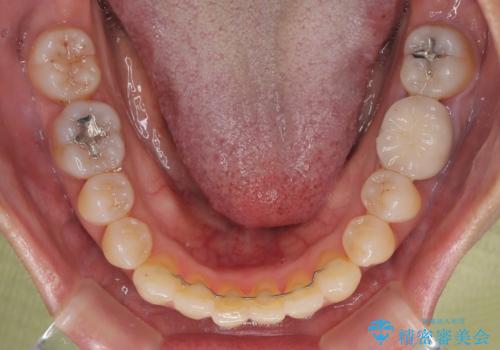

受け口と八重歯を改善 インビザライン矯正治療

受け口傾向の骨格であり、前歯はクロスバイトまたは切端咬合となっており、下顎を中心に歯列全体の後方移動を行い、IPR(歯と歯の間を削る)によってデコボコが解消するように設計し、インビザラインにより治療を行うこととしました。

受け口傾向のインビザライン矯正は比較的治療を行いやすいため、きれいに仕上げることができました。舌の突出癖が顕著であったため、改善のためのトレーニングをしっかりと行っていただきました。